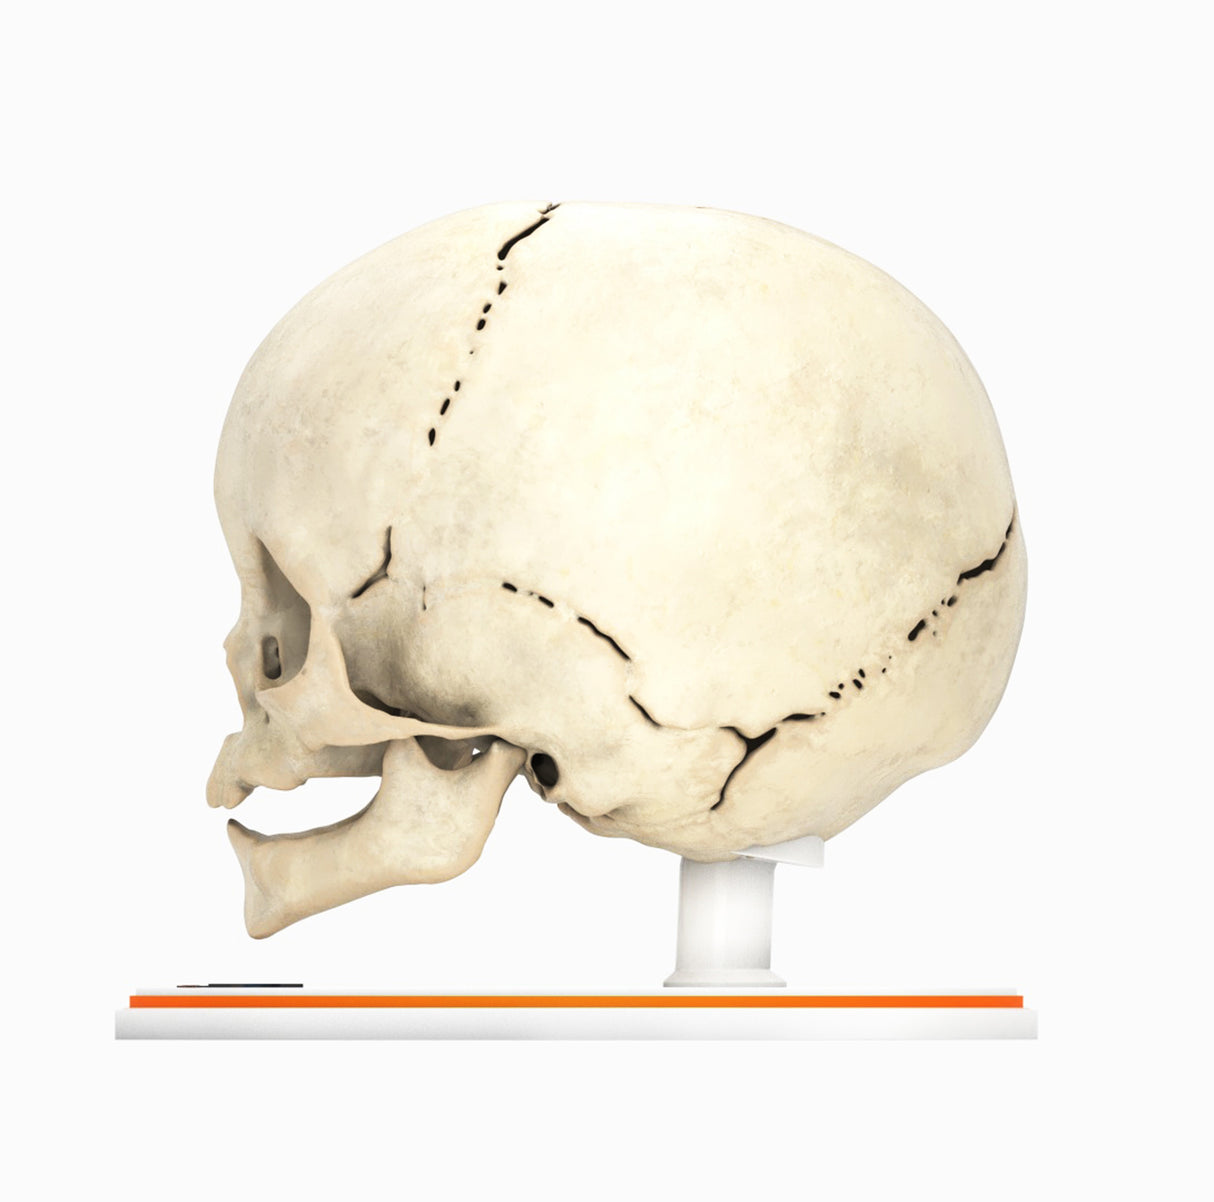

Infant Skull With Craniosynostosis of the Metopic Suture - Male, 8 Months

Infant Skull With Craniosynostosis of the Metopic Suture - Male, 8 Months

Craniosynostosis, a condition in which one or more cranial sutures in the infant skull prematurely mineralize and fuse before completion of brain development, with affected sutures:

Metopic synostosis (trigonocephaly) – The metopic suture separates two frontal bones in the cranial vault and runs from the nose to the sagittal suture at the top of the head. Premature fusion causes a triangular head shape, narrow in the front and broad in the back, with a metopic ridge at the midline of the forehead.

In most cases, the cause of craniosynostosis is unknown. Crouzon, Apert and Pfeiffer syndromes are the most common craniofacial syndromes, accounting for nearly two-thirds of syndromic cases. Most of these patients exhibit elevated intracranial pressure (ICP), hydrocephalus, optic atrophy, and respiratory, speech and hearing problems. Surgical management is common for primary craniosynostosis where there is restriction of brain growth and elevated ICP, typically within the first year of life.

Designed using MRI and CT imaging scans and the latest 3D printing technologies, in collaboration with Mayo Clinic.